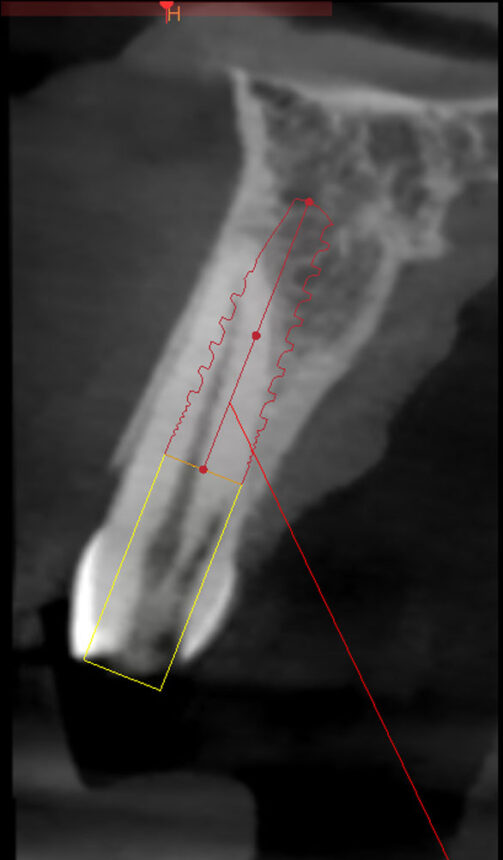

Στο περιστατικό που θα αντιμετωπιστεί live θα γίνει άμεση τοποθέτηση εμφυτεύματος με πλήρη καθοδήγηση χειρουργικού νάρθηκα, θα συζητηθούν οι εναλλακτικές προσεγγίσεις και θα παρουσιαστεί ο τρόπος και τα διαφορετικά σενάρια εξατομίκευσης της επούλωσης των μαλακών ιστών.

- Παρουσίαση του πρωτόκολλου τρυπανισμού και ελέγχου με το νάρθηκα κατευθυνόμενης τοποθέτησης,